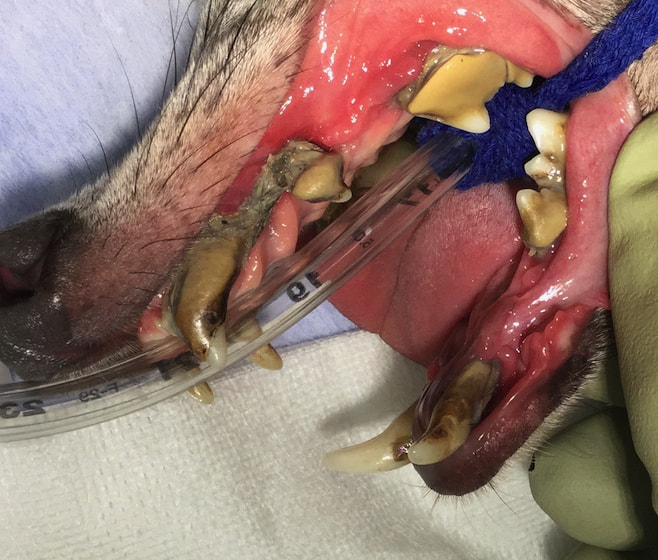

犬の慢性潰瘍性歯周口内炎(2025/11/10)

犬の慢性潰瘍性歯周口内炎は、歯に接する口腔粘膜の持続的な炎症と痛みを特徴する病気です。根本的な病態は解明されていませんが、歯垢の中に存在する細菌に対する過剰な免疫反応が主な原因と考えられています。症状としては、口臭、流涎、歯ぐきや口腔粘膜からの出血や潰瘍、強い痛みなどがよく認められます。徹底的な歯垢除去とその後の継続的なホームケアが治療の要となりますが、清潔な状態が維持できないと歯垢蓄積後の再発も非常に多く、抜歯が最も有効な選択肢となることもあります。採食中やご自宅でのデンタルケアの間などで口に痛みを感じている様子がある場合は、お早めにご相談下さい。

獣医師 臼井